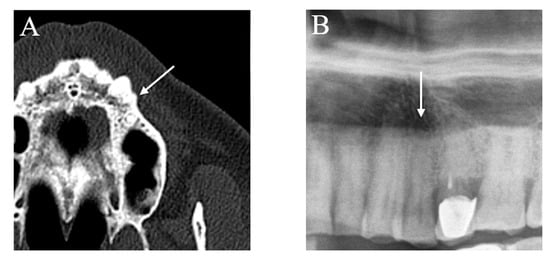

No false positive or false negative was found in the assessment of deep caries, root remnants, and stage III periodontal disease, whereas false positives were very few (2.6%) (Figure 2) and false negatives accounted for just over half of the cases (53.2%) for AP lesions (Figure 3).

Figure 2.

An example of false-positive apical periodontitis. (A) Upper jaw MSCT imaging. No periapical bone lesion was detected (arrow). (B) In PAN, at the level of the periapex of the root of the left first premolar, the observers noted a radiolucent periapical image (arrow) characterised by supposed changes in bone structure that simulated an apical periodontitis lesion.